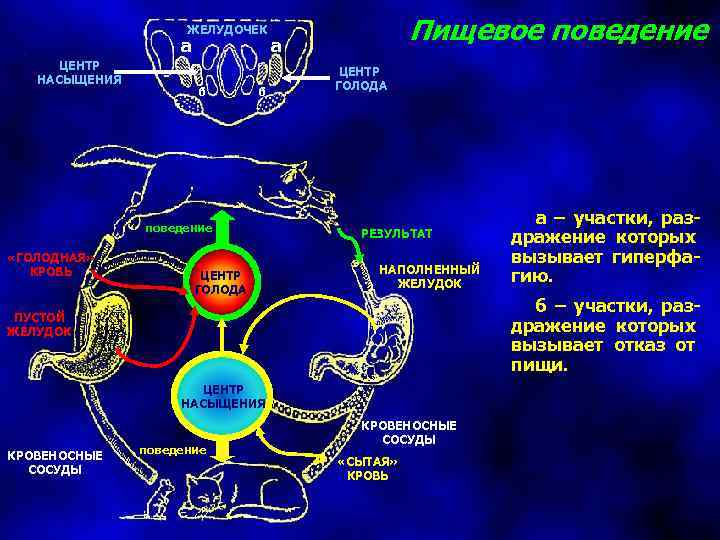

Как работает центр насыщения в гипоталамусе: визуальные иллюстрации